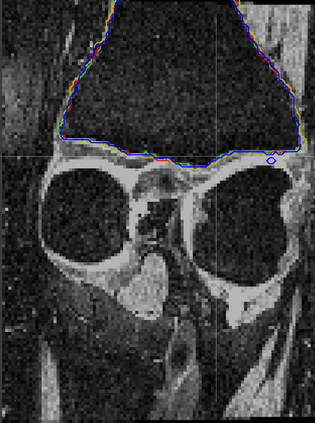

Direct automatic segmentation of objects from 3D medical imaging, such as magnetic resonance (MR) imaging, is challenging as it often involves accurately identifying a number of individual objects with complex geometries within a large volume under investigation. To address these challenges, most deep learning approaches typically enhance their learning capability by substantially increasing the complexity or the number of trainable parameters within their models. Consequently, these models generally require long inference time on standard workstations operating clinical MR systems and are restricted to high-performance computing hardware due to their large memory requirement. Further, to fit 3D dataset through these large models using limited computer memory, trade-off techniques such as patch-wise training are often used which sacrifice the fine-scale geometric information from input images which could be clinically significant for diagnostic purposes. To address these challenges, we present a compact convolutional neural network with a shallow memory footprint to efficiently reduce the number of model parameters required for state-of-art performance. This is critical for practical employment as most clinical environments only have low-end hardware with limited computing power and memory. The proposed network can maintain data integrity by directly processing large full-size 3D input volumes with no patches required and significantly reduces the computational time required for both training and inference. We also propose a novel loss function with extra shape constraint to improve the accuracy for imbalanced classes in 3D MR images.

翻译:3D医学成像的物体,如磁共振成像(MR)成像的直接自动分离,具有挑战性,因为往往需要精确地确定大量调查中大量存在复杂地理不对称的单个物体。为了应对这些挑战,大多数深层学习方法通常会大大提高其模型内可训练参数的复杂性或数量,从而提高其学习能力。因此,这些模型一般需要在运行临床MR系统的标准工作站上花很长的推断时间,并限于高性能的计算机硬件,因为它们的记忆要求很大。此外,要在这些大型模型中安装3D数据集,还要利用有限的计算机记忆,经常使用交换技术,例如补对称培训等,以牺牲从对诊断目的具有临床重要性的投入图像中获得的精细比例的几何地理信息。为了应对这些挑战,我们提出一个具有浅度记忆足迹的银色网络,以有效减少为状态性能所需的模型参数数量。这对于实际就业至关重要,因为大多数临床环境只有低端硬件,计算机功能和记忆有限。拟议的网络可以通过直接处理全尺寸三维化技术来保持数据的完整性,直接处理全尺寸的全尺寸三维的图像,从而大幅改进所需的超度变压的磁度计算。